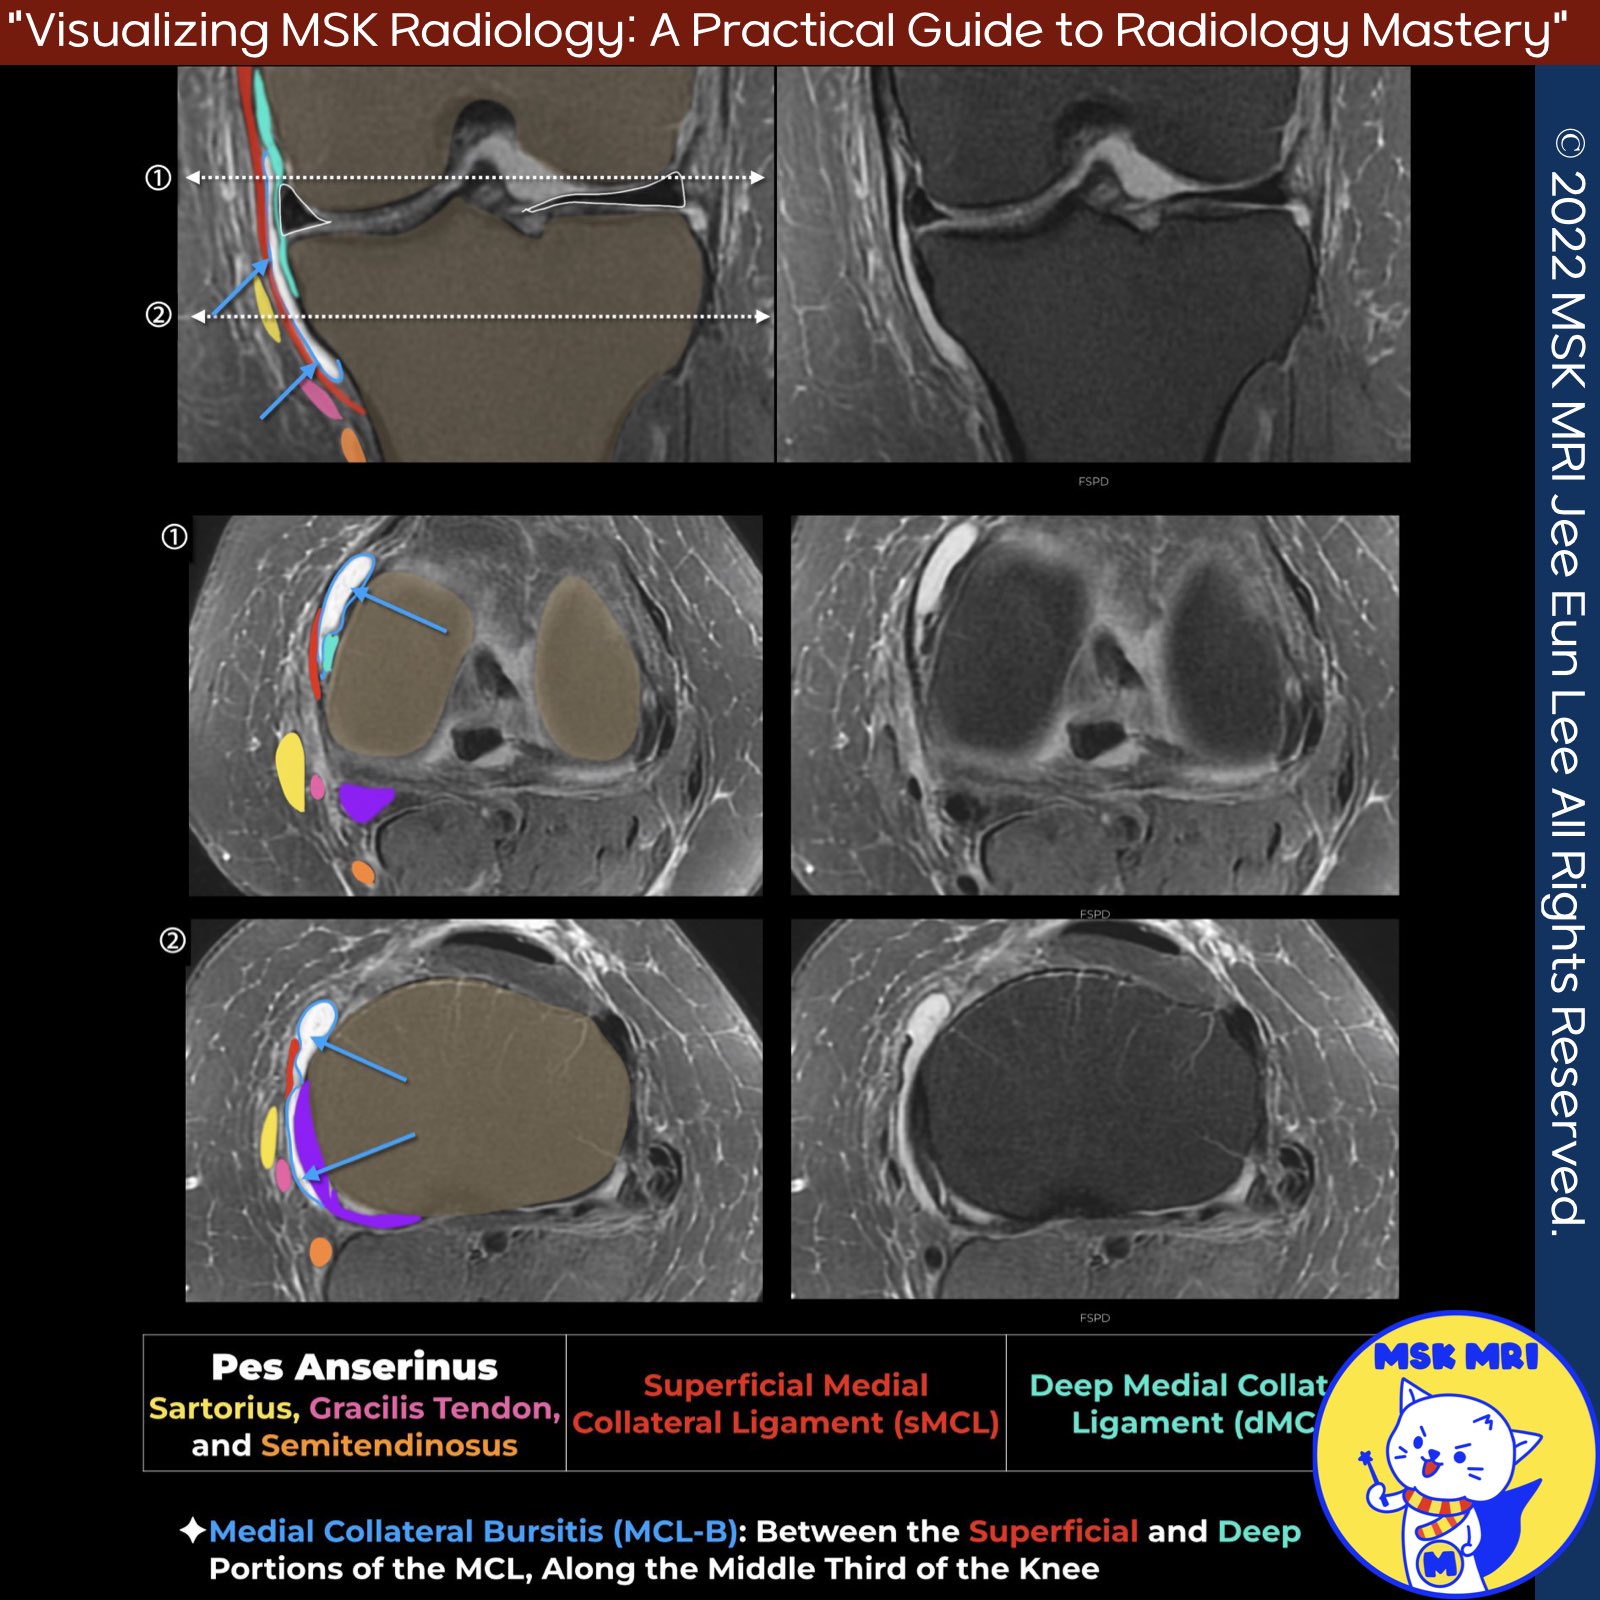

✅ Anatomy of the MCL Bursa

- Located between superficial and deep portions of the MCL along the middle third of the knee joint

- May be single or multi-compartment

✅Imaging Findings of MCL Bursitis

- Well-defined fluid collection

- May extend into femoral/tibial compartments adjacent to cortex

- Anterior margin adjacent to MCL

- Posterior margin at MCL-deep capsular ligament junction

- Fine septations within bursal fluid

- Can communicate with semimembranosus-tibial bursa

✅Distinguishing MCL Bursitis from Grade I MCL Injury

★ Grade I MCL Injury

- High signal edema outlining the superficial medial collateral ligament (MCL) without ligamentous disruption

★ MCL Bursitis

- Fluid-filled lesion between superficial and deep MCL

- Normal MCL thickness and signal intensity

- No surrounding edema